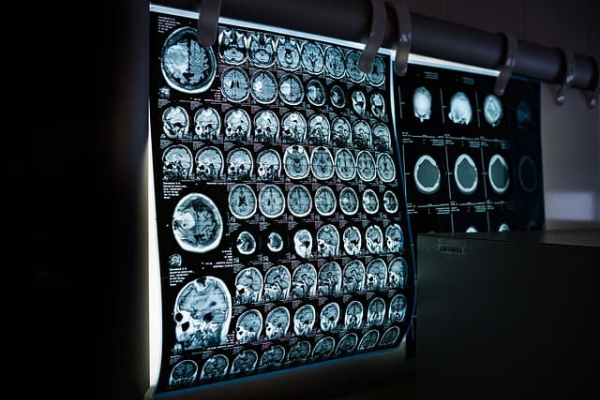

MRI(Magnetic Resonance Imaging)는 강한 자기장과 고주파를 이용해 인체 조직의 수소 원자 반응을 영상화하는 기술입니다.

연부조직, 신경, 인대, 연골 등 미세한 구조를 매우 정밀하게 확인할 수 있어 디스크, 뇌질환, 암 등에서 필수 검사입니다.

- 뇌졸중, 뇌종양, 다발성 경화증 진단

- 허리디스크, 척추 협착증, 관절 연골 손상

- 자궁근종, 난소 종양, 전립선 질환